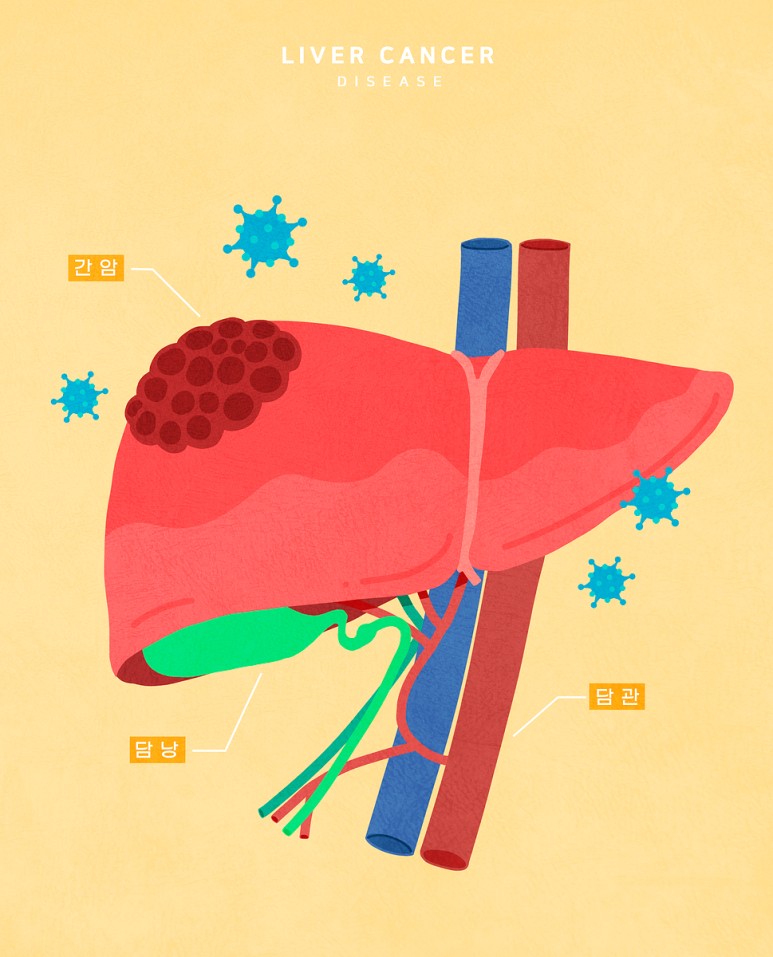

담석증은 우리가 흔히 담낭이라 불리는 담낭에 저장된 액체가 돌조각처럼 딱딱하게 굳어져 형성되는 것을 말합니다.담낭은 작은 주머니 모양의 구조로 복부의 오른쪽 상단, 간 아래에 위치하고 있습니다.담즙이라 불리는 액체는 지방의 소화를 돕기 위해 필요한데, 간에서 생성된 후 담낭 속에 저장돼 우리가 밥을 먹을 때 담낭이 수축되면서 총담간이라 불리는 관에 담즙을 눌러 십이지장에 담즙이 배출돼 음식물의 소화를 돕게 됩니다.

담석은 크게 콜레스테롤성 담석과 색소성 담석으로 나뉘는데, 각각의 담석의 증원인은 다르다고 할 수 있습니다.콜레스테롤성 담석은 담즙이 함유된 성분 중 콜레스테롤의 양이 증가하여 발생하는 것을 말하며 각종 감염이나 만성 간질환, 위절제수술 등으로 인한 췌장관계 변화에 의해서도 발생할 수 있어 보다 각별한 주의와 관리가 필요합니다.색소성 담석은 주로 세균 감염에 의해 발생하는데, 간경변이 있는 환자나 담도 계통의 염증이 있는 환자, 겸상적 혈구성 빈혈과 같은 유전적 혈액질환이 있는 환자에게서 쉽게 발생합니다.